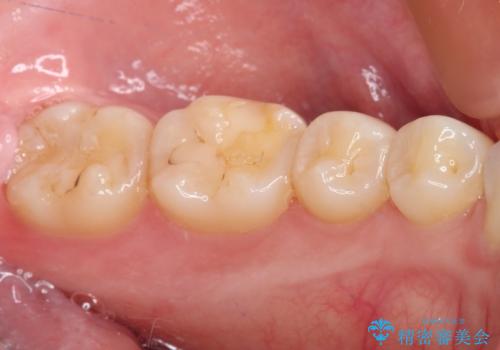

冷たいものがしみる症状はなくなり、舌で触ったときのザラザラ感もなくなりました。